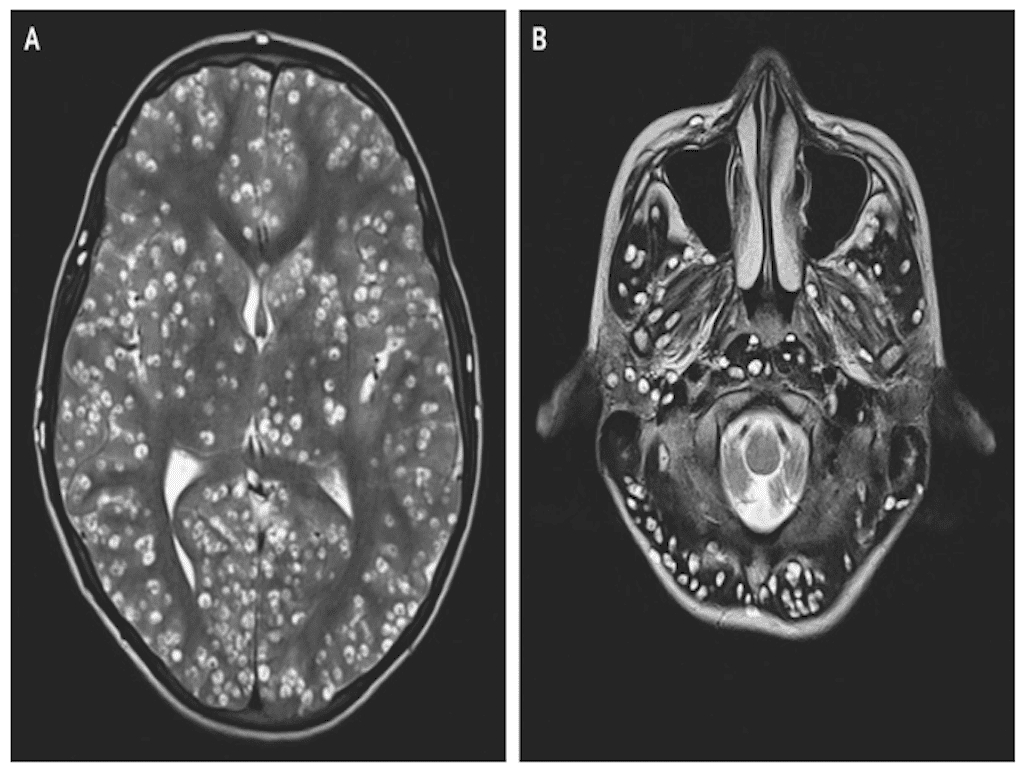

Ce sont les parents du malade qui l’ont conduit à l’hôpital de Faridabab. Car le jeune homme souffre énormément du côté de droit de l’aine et fait des crises d’épilepsie régulières, indiquent-ils aux médecins. Ces derniers lui font donc passer une IRM et une échographie. Ils découvrent alors que son cervelet, son tronc cérébral et son cortex cérébral sont plein de larves en train de s’enkyster. Le malheureux est également atteint à l'oeil droit et à la testicule gauche.

Diagnostic : le patient souffre de neurocysticercose, une infection infection parasitaire du système nerveux central provoquée par un ver plat appelé le ténia du porc (Taenia solium). Si cette maladie a déjà été observée par les médecins, elle est ici particulièrement avancée. Le jeune homme est si atteint que les spécialistes ne peuvent pas lui donner d’antiparasitaire de peur d’aggraver sa pression intracrânienne déjà très élevée. Dans l’espoir de réduire l’inflammation et de contrôler les crises d’épilepsie, ils lui prescrivent donc un corticoïde. En vain, le jeune homme est déjà bien trop atteint. Il décède deux semaines après sa visite à l’hôpital.